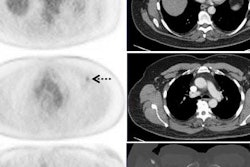

Images are from an 8-year-old girl with right humeral osteosarcoma. SUVmax declined from 14.9 at baseline to 9.0 after five weeks of therapy and then rose slightly to 9.8 after 10 weeks of therapy. The resected tumor specimen was 61% necrotic. The patient died of recurrent disease approximately 15 months after diagnosis. Images courtesy of JNM.The researchers also calculated receiver operating characteristic (ROC) curves for SUVmax at five and 10 weeks and based on the percentage change from baseline to week 10. Optimum cutoff points for SUVmax were 4.04 at week 5 and 3.15 at week 10, along with a 60.24% decrease from baseline at week 10. Based on those values, the SUVmax parameters achieved high sensitivity.